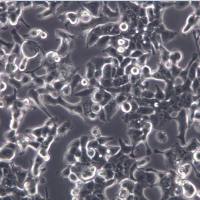

细胞名称:Bcap-37 人乳腺癌细胞

组织来源:乳腺

培养条件:1640 +10% FBS

形 态:贴壁;上皮细胞样